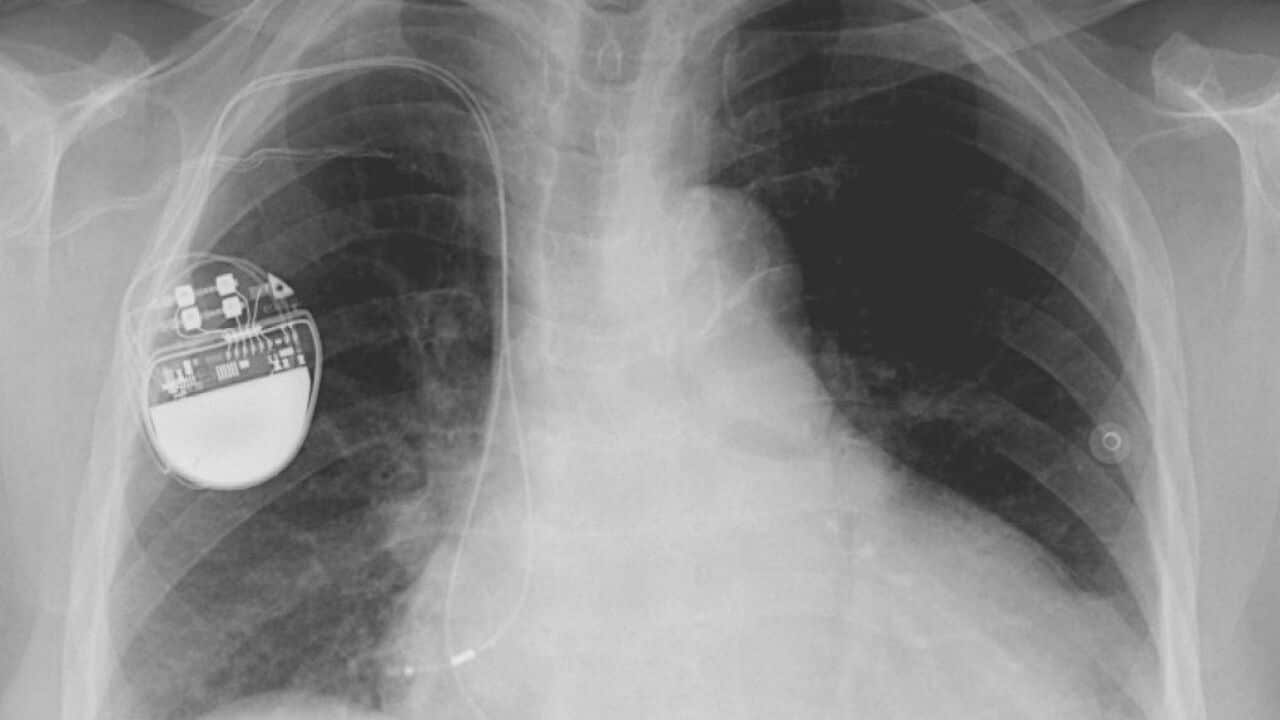

另外,林教授也解答大家的電話提問,包括有人問 60 多歲的長者需要進行心瓣膜 (heart valve) 置換手術。醫生給了兩大方案 —— 牛心瓣膜或金屬心瓣膜。林教授解釋兩者的利弊。